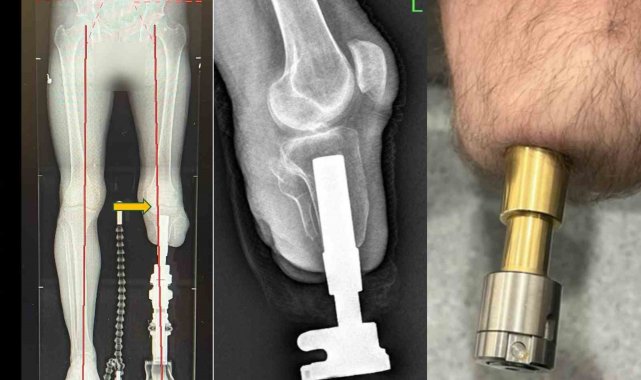

Klasik soket protezlerin yol açtığı ağrı, yara ve yürüme zorluklarına bir alternatif sunan osseointegrasyon yöntemi, amputasyon hastalarına umut veriyor. Medipol Mega Üniversite Hastanesi Ortopedi ve Travmatoloji Uzmanı Prof. Dr. Adnan Kara, Türkiye'de yeni nesil osseointegrasyon protezini ekipleriyle uygulayan ilk merkez olduklarını belirterek, "Bu yöntemle hastalar adeta kendi bacaklarıyla yürüme hissine kavuşuyor" dedi. Bu yöntemde, kemiğe yerleştirilen implant sayesinde yük doğrudan kemiğe aktarıldığından, çok daha doğal ve konforlu bir yürüyüş mümkün oluyor.

Osseointegrasyon yönteminin dünyada sayılı merkezlerde uygulandığını vurgulayan Prof. Dr. Kara, "Bu işlem sadece ortopedik cerrah ile değil, fizik tedavi uzmanı, anestezi hekimi ve deneyimli fizyoterapistlerden oluşan bir ekip ile mümkün. Multidisipliner bir yaklaşımla başarılı sonuçlar alıyoruz" diye konuştu. Osseointegrasyon protezinden kimlerinfaydalanabileceğine de değinen Prof. Dr. Kara, yöntemin en çok daha önce soket protez kullanmış ancak çeşitli sorunlar yaşamış genç ve aktif hastalara önerildiğini söyledi. "Ciltte yara oluşumu, yürüyüş sırasında ağrı, uyumsuzluk nedeniyle erken yorulma gibi sorunlarla bize gelen hastalarda bu yöntem oldukça etkili. Klasik protezlerle sadece birkaç dakika yürüyebilen hastalar, bu yeni sistemle hayatlarına tekrar karışabiliyor" dedi.

Osseointegrasyon protezlerinin getirdiği his avantajına da değinen Prof. Dr. Kara, "Bu yöntemle hastalar bir yıl içerisinde bastıkları zeminin kum, çakıl ya da düz olup olmadığını ayırt edebiliyor. Hislerin kemiğe iletildiği veriler sayesinde vücut o bacağı kendi uzvu gibi hissediyor. Bu da hastanın yürüyüşünü ve psikolojisini büyük ölçüde olumlu etkiliyor" dedi. Osseointegrasyon protezlerinin yapıldığı uzuvlar hakkında da bilgi veren Prof. Dr. Kara, yöntemin uyluk, kaval kemiği, dizüstü ve dizaltı gibi bölgelerin yanı sıra üst kol amputasyonlarında da başarıyla uygulandığını aktardı.